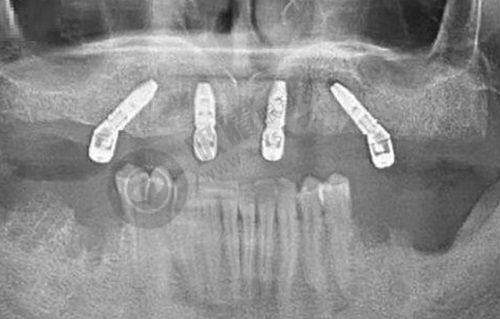

口腔外科:是浙江省成立较早、规模较大、技术力量雄厚的科室,为浙江省口腔颌面外科发源地。两院区共有床位82张,拥有进口腔综合治疗台10张。年门诊量、急诊人数、住院人数、手术总量、重大疑难手术总量和疾病难度系数一直为全省之首。开展的项目包括口腔颌面部疾病、颅颌面创伤、口腔颌面部缺损的整复重建、口腔种植、颞下颌关节疾病、颌面部畸形的外科治疗等。

刘雁鸣:口腔颌面外科骨干医生,临床工作经验20多年,擅长种植牙技术以及种植前牙槽外科如上颌窦提升术、牙槽嵴增高术等;颌面部各种肿 瘤的手术治疗;颅颌面部创伤的治疗;颌面部缺损的手术重建。